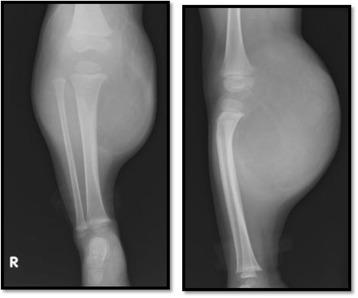

Our patient was a 23-month-old Japanese girl. At 6 months of age, she presented at a nearby hospital with a mass on the popliteal side of her lower right leg. She had no symptoms and was diagnosed as having a benign adipose tumor via magnetic resonance imaging. The mass gradually increased in size, and she was referred to our hospital at 1 year and 11 months of age. A physical examination and radiology revealed a localized mass 13 × 10 × 7 cm in size in the aforementioned area that restricted knee movement and caused proximal tibia deformity. Magnetic resonance imaging showed a giant circumscribed subcutaneous mass with multiple partitions that was hyperintense on T1-weighted and T2-weighted images but not fat-saturated on T2-weighted images. Based on these findings, she was diagnosed as having a lipoblastoma. Because the mass surrounded her popliteal artery and vein and part of the popliteal nerve, surgical resection was considered risky, and we opted to simply observe her. However, owing to rapid growth of the mass and the worsening of symptoms, she underwent complete resection at 2 years and 6 months of age. A histological examination confirmed the diagnosis of a lipoblastoma. She was discharged from our hospital 3 days after surgery with no symptoms. She could walk without pain at the 6-month follow-up, and no local recurrence was observed.

我们的患者是一名23个月大的日本女孩。6个月大时,她因右下肢腘窝处有一肿块就诊于附近医院。她没有症状,通过磁共振成像被诊断为良性脂肪肿瘤。肿块逐渐增大,1岁11个月时被转诊至我院。体格检查和影像学检查显示,上述区域有一个大小为13×10×7 cm的局限性肿块,限制了膝关节活动并导致胫骨近端畸形。磁共振成像显示一个巨大的边界清晰的皮下肿块,有多个分隔,在T1加权和T2加权图像上呈高信号,但在T2加权图像上未脂肪抑制。基于这些发现,她被诊断为脂肪母细胞瘤。由于肿块包绕了她的腘动脉、静脉和部分腘神经,手术切除被认为有风险,我们选择先对她进行观察。然而,由于肿块迅速生长且症状加重,她在2岁6个月时接受了完整切除。组织学检查确诊为脂肪母细胞瘤。术后3天她从我院出院,没有症状。6个月随访时她能无痛行走,未观察到局部复发。